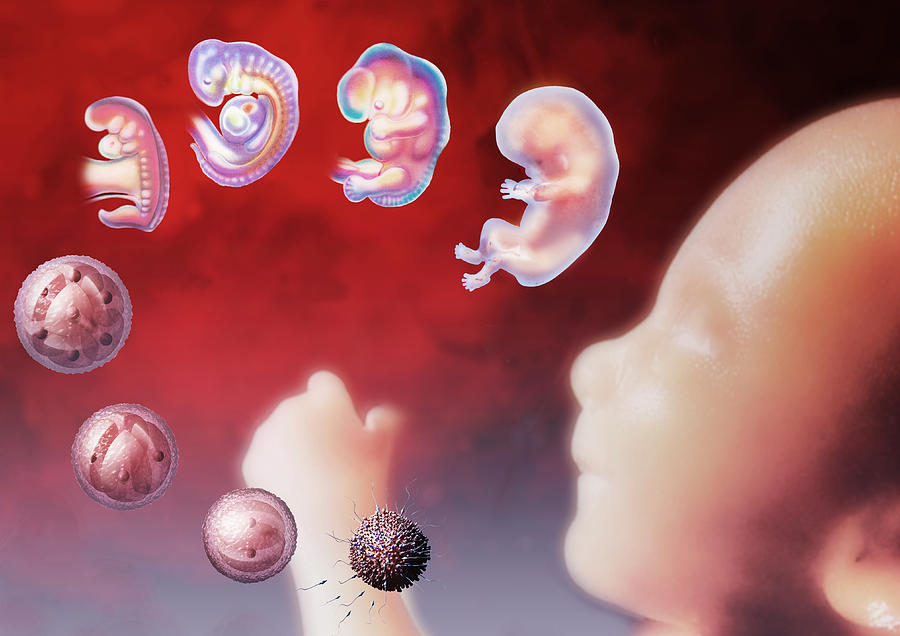

wallpaperaccess.comStages Of Embryo Development

wallpaperaccess.comStages Of Embryo Development

www.rmany.comEmbryo, 46 Days - Stock Image - C048/7912 - Science Photo Library

www.rmany.comEmbryo, 46 Days - Stock Image - C048/7912 - Science Photo Library